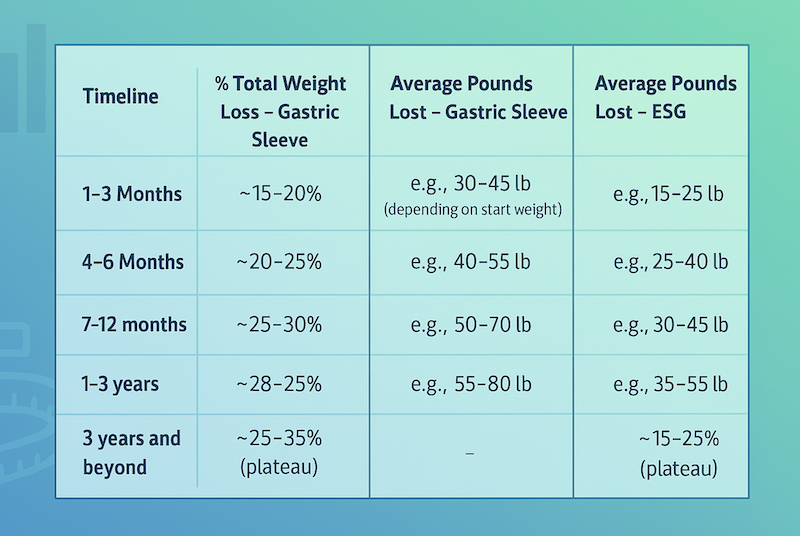

View Article Gastric Sleeve Weight Loss Chart + Timeline: What to Expect

View Article Gastric Sleeve Weight Loss Chart + Timeline: What to Expect Gastric Sleeve Weight Loss Chart + Timeline: What to Expect